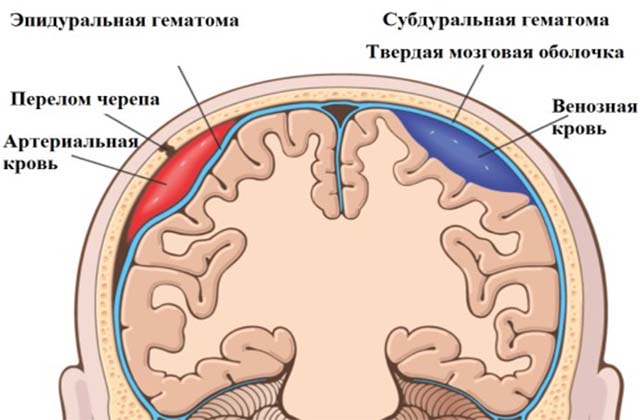

Гематома эпидуральная

Такие образования возникают из-за разрыва сосудов, находящихся между мозговой оболочкой и черепной костью. Если диагностирована эпидуральная гематома у новорожденного после родов, последствия ее довольно опасны. Уже через 5-7 часов в мозговых тканях может возникнуть существенное их сдавливание, вследствие чего состояние малыша стремительно ухудшается.

По форме образования эпидурального типа похожи на линзу 3-8 см в диаметре. По степени тяжести различают три формы:

- Легкая, когда меньше 100 мл составляет объем крови.

- Средняя. Накапливается до 150 мл крови.

- Тяжелая. Вследствие кровоизлияния в гематоме содержится 200 мл жидкости и больше.

Гематомы субдуральные

При разрывах сосудов между мягкой и твердой оболочкой черепной коробки образуется гематома в голове после родов у новорожденного, которая называется субдуральной.

3) Епидуральная гематома считается наиболее неблагоприятной, так как у ребенка происходит разрыв артерии между твердой оболочкой мозга и костью черепа. Разрыв сосуда в таком случае возникает из-за перелома черепа. Массивное кровоизлияние приводит к тому, что кровь оказывает сильное давление на ткань мозга, а это становится причиной комы и летального исхода при несвоевременно начатом лечении. При эпидуральной гематоме проводится хирургическая операция.

4) Субдуральная гематома: кровь скапливается под твердой оболочкой мозга. Тактика лечения патологии зависит от степени ее тяжести. При небольшой субдуральной гематоме назначаются препараты для восстановления кровоснабжения мозга (Курантил, Эуфиллин). Крупная гематома требует хирургического лечения.